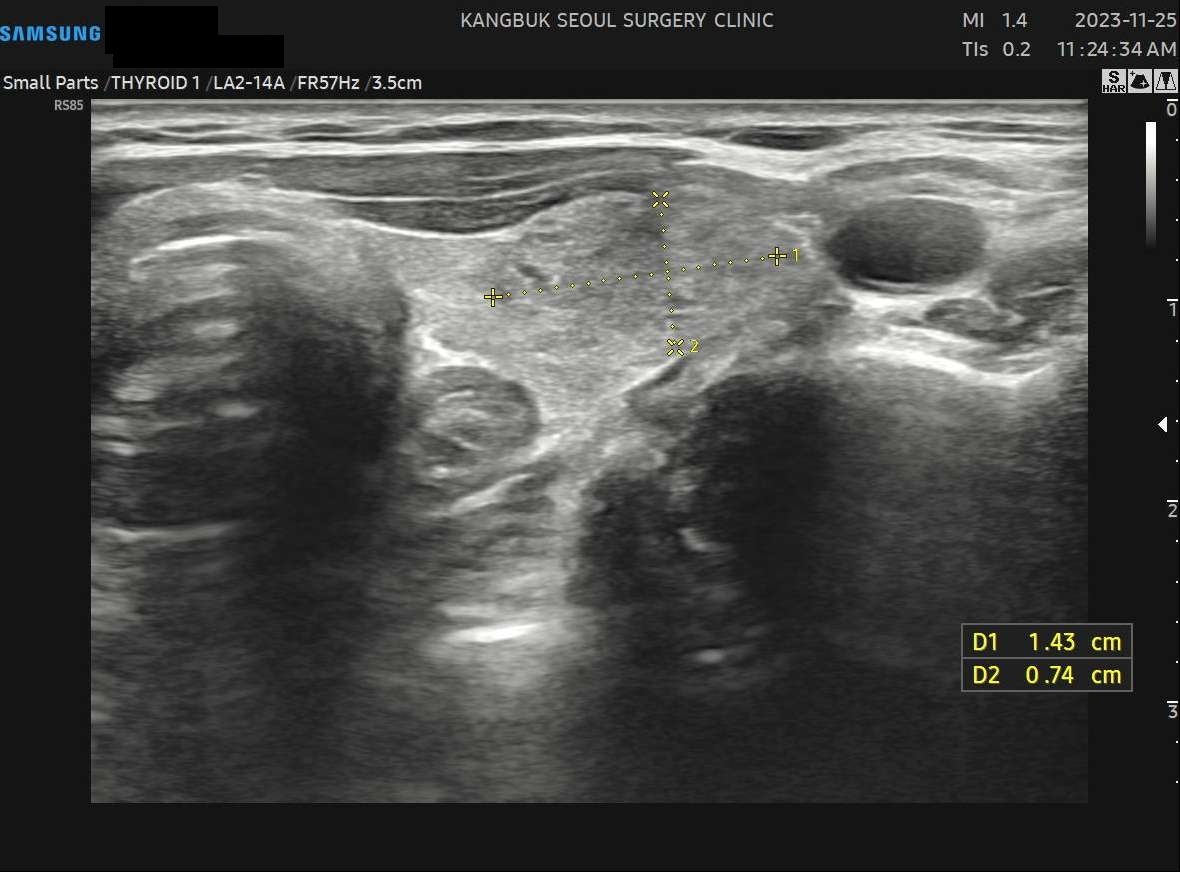

사례 1

수술 8개월 후(1.43cm)